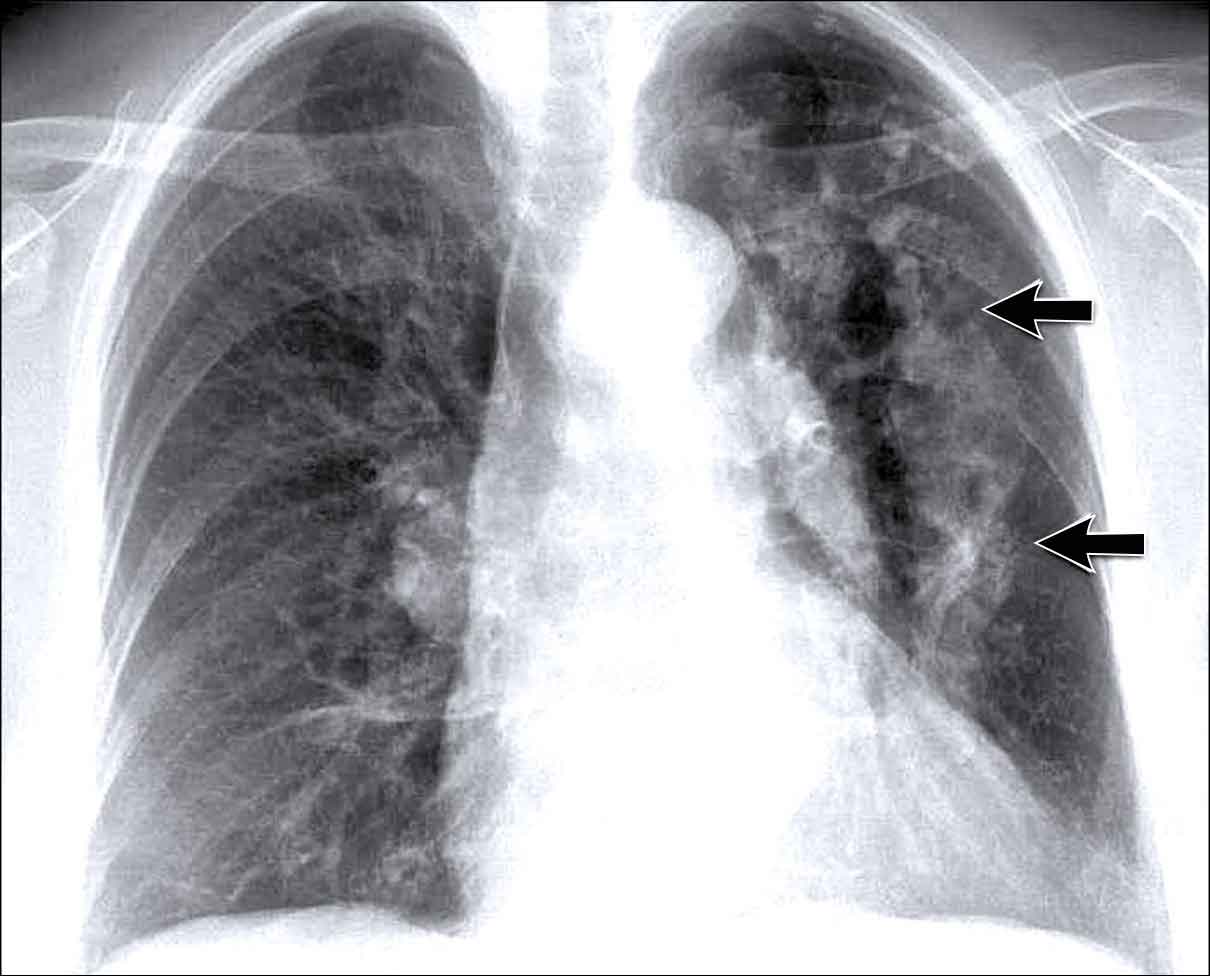

Hilar enlargement - case 1

In this case there is an enlarged hilar shadow on both sides.

This could be the result of enlarged vessels or enlarged lymph nodes.

A very helpful finding in this case is the mass on the right of the trachea.

This is known as the 1-2-3 sign in sarcoidosis, i.e. enlargement of left hilum, right hilum and paratracheal.

Here some more examples of sarcoidosis.

Click image to enlarge.

1. Lymphadenopathy and groundglass appearance of the lungs

2. Lymphadenopathy, 1-2-3 sign

3. Bulky lymphadenopathy

4. 1-2-3 sign

5. Nodular lung pattern, no lymphadenopathy

6. Hilar and paratracheal lymphadenopathy